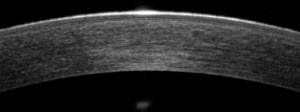

Es mas, la tecnología de la que disponemos ,TOPOGRAFOS de ultima generación ,que nos dan información del astigmatismo de cara anterior y posterior de nuestra cornea y OCT anterior (tomografía de coherencia óptica), que permite, mediante un haz de láser infrarrojo, obtener una imagen microscópica y en tres dimensiones de la córnea. Gracias “podemos ver cómo la lente de contacto se apoya en cada punto de la córnea de forma objetiva y, por tanto, diseñarla absolutamente a medida”, nos facilita en todo momento las adaptaciones complicadas y no tan complicadas.